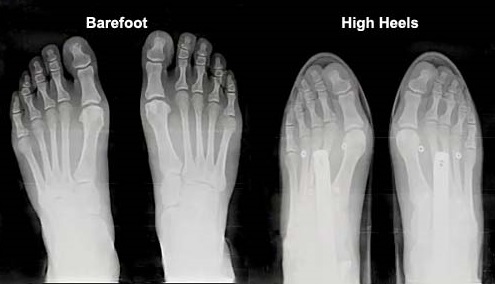

Also foot shape is completely changed with modern shoes: as Figure 6 highlights, considering the effect of bone remodeling, frequent shoes wearing causes the feet to develop differently from what nature intended for us. Barefoot walkers have wider feet and more equally distributed peak pressures. Habitually shod subjects have relatively short and slender feet, with non-homogeneous pressure distribution [26]. So, it is not surprising that many foot disorders are typical only of shod populations [27,28], such as flatfoot and fallen arches, bunions and hallux valgus, hammer toe, blisters, corns and calluses.

BarefootShodStructure1

Figure 6 – Difference in the foot shape between barefoot and high-heeled shoes. Over long time, this causes deformities from the ideal natural shape of the foot. (From [33])